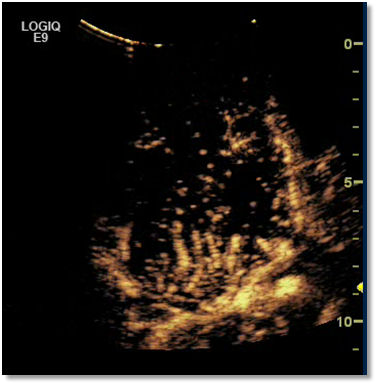

Contrast ultrasound agents improve the display of vascularity of liver lesions. resulting in a more specific lesion characterisation.

Focal liver lesions have a specific vascular supply which is characteristic for the specific lesion type and usually different from normal liver tissue with an early and weak arterial enhancement and a stronger portal-venous and late enhancement.

The abnormal (chaotic) vascularity of the hepatocellular carcinoma (HCC) can easily be demonstrated at the very early contrast inflow phase. Liver metastases can be characterised reliably in the late phase.

The advantage of CEUS is that all phases (from the very early arterial phase to the late phase 6-8 min after injection) can be continuously seen, so that no relevant phases and patterns are missed.